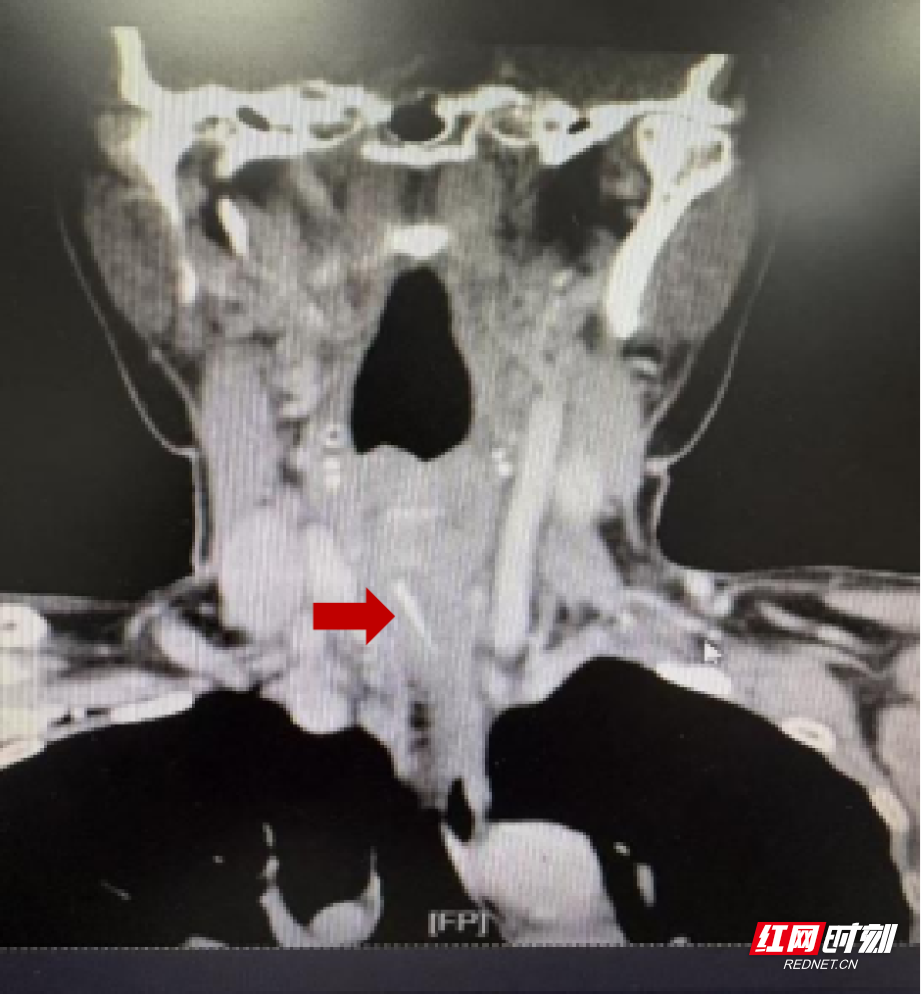

据了解,1月23日,该女士在进食时不慎吞入鱼刺。随后,她尝试了吞饭团等民间方法,试图将鱼刺压下,结果反而使其扎得更深。三天内,她辗转多家医院,接受了食道镜、胃镜检查,均未能将鱼刺取出。1月26日,她来到中南大学湘雅三医院时,鱼刺已穿透食管壁,移行至颈部深层组织,紧邻颈总动脉及重要神经束,随时可能刺破血管引发致命性大出血。

情况危急。该院耳鼻咽喉头颈外科副主任医师陈江波、艾金刚团队评估后,于次日为患者实施颈侧切开探查手术。术中,医生沿颈部自然皮纹切开约5厘米切口,逐层分离,最终在食管外寻获并完整取出了这根潜伏长达5天的鱼刺。术后,经抗感染、营养支持等精心治疗与护理,患者恢复良好,目前已康复出院。